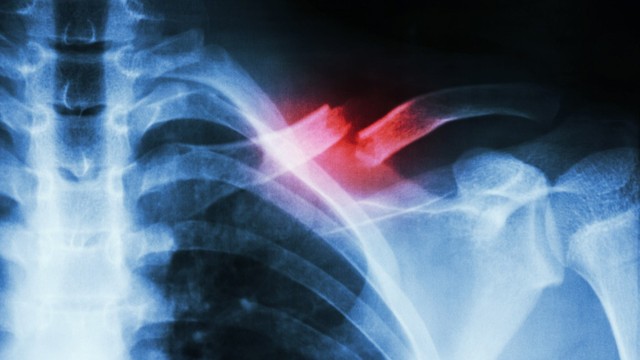

:format(webp)/bi_gay_xuong_don_bao_lau_thi_lanh_Ru_H_Of_1659763248_7015875f18.jpg)

Bị gãy xương đòn bao lâu thì lành là câu hỏi được nhiều người quan tâm. Bởi trong cuộc sống sinh hoạt và lao động, xương đòn vai có thể bị gãy do nhiều nguyên nhân khác nhau. Tùy thuộc vào tình trạng xương bị tổn thương mà thời gian điều trị và hồi phục cũng sẽ khác nhau.